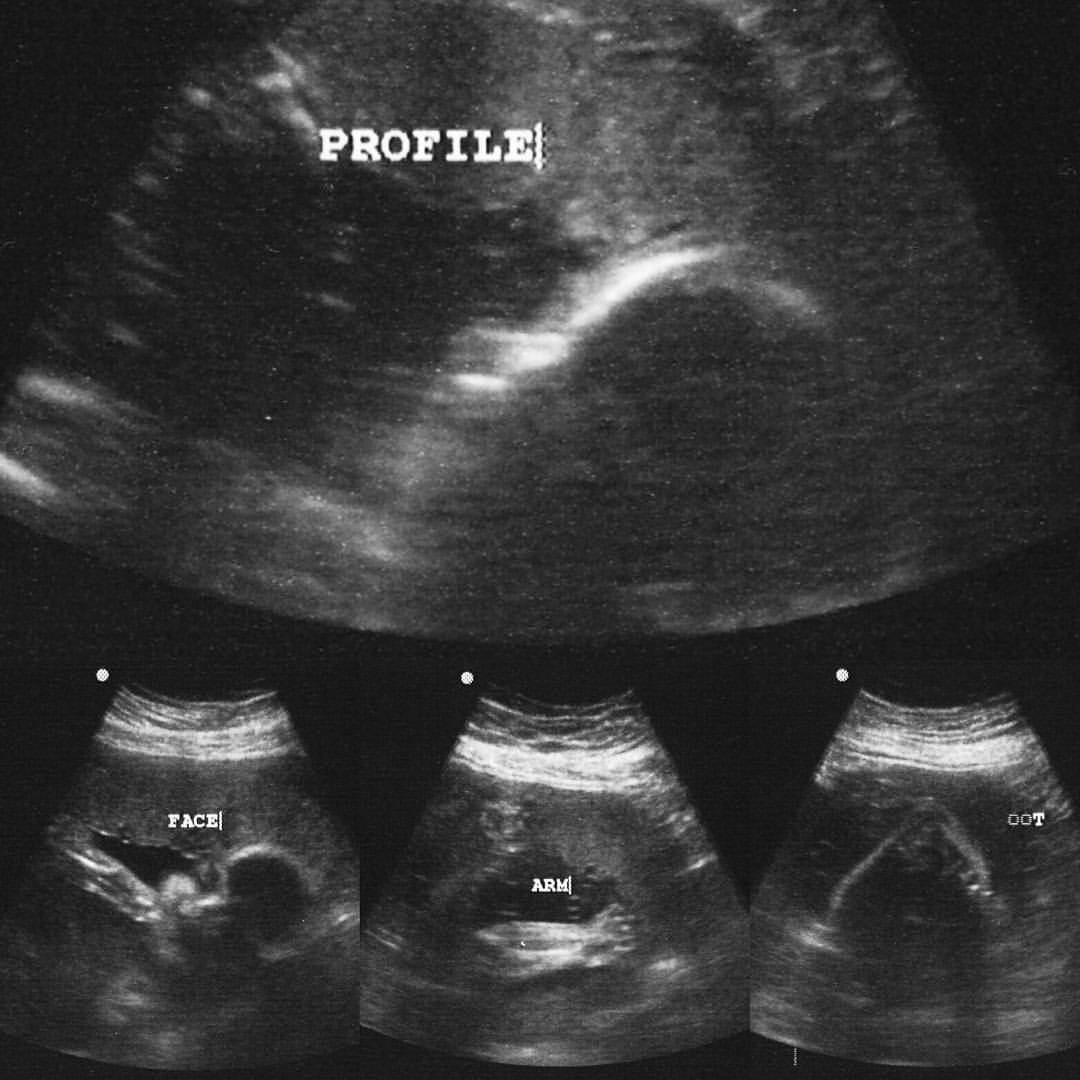

Clint & I headed to our ultrasound & I actually got to enjoy seeing our little guy because I was so numbed up. 🙂

After the ultrasound, we went straight back to the dentist & they pulled my tooth. As I laid there & felt them yanking on my tooth & jaw, I couldn’t help but just think about my little guy & his cute little movements that I got to see just an hour before. It definitely helped get me through that moment &, again, reminded me that this crappy, crappy moment of pain would pass!